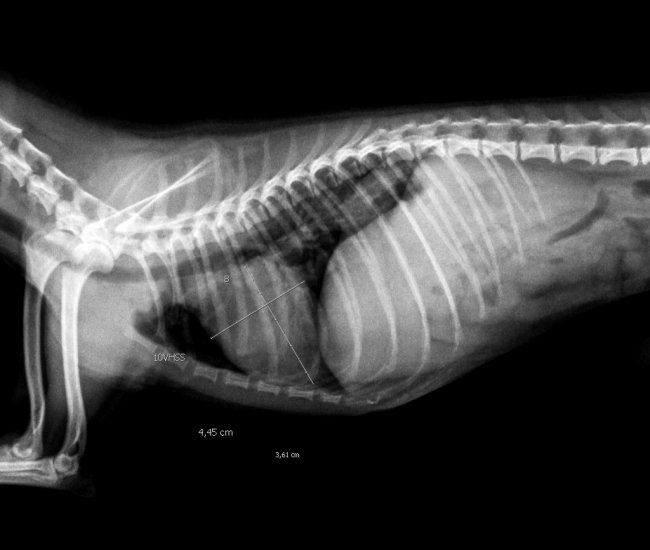

- Diferentemente do raio-x analógico, este raio-x oferece altíssima definição e todas as vantagens da tecnologia digital. É possível aproximar a imagem, trabalhar o contraste, exposição.O software permite ainda avaliações da medida cardíaca do animal e graus de displasia coxofemoral, por exemplo – explica o Dr. Nardeli Lucena.

- sofware com medidas para avaliações do tamanho cardíaco e medições dos ângulos de Norberg para diagnóstico e classificação de displasias coxofemorais;